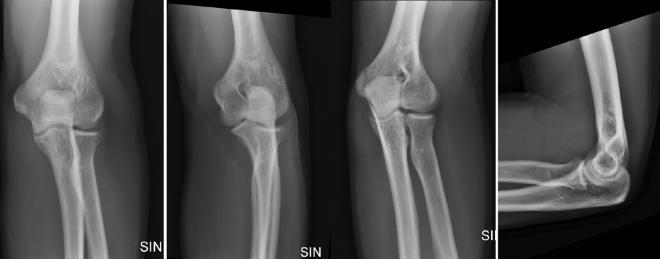

Joint effusion due to elbow fractures are common among adults and children. Radiography is the most commonly used imaging procedure to diagnose elbow injuries. The purpose of the study was to investigate the diagnostic accuracy of deep convolutional neural network algorithms in joint effusion classification in pediatric and adult elbow radiographs. This retrospective study consisted of a total of 4423 radiographs in a 3-year period from 2017 to 2020. Data was randomly separated into training (n = 2672), validation (n = 892) and test set (n = 859). Two models using VGG16 as the base architecture were trained with either only lateral projection or with four projections (AP, LAT and Obliques). Three radiologists evaluated joint effusion separately on the test set. Accuracy, precision, recall, specificity, F1 measure, Cohen's kappa, and two-sided 95% confidence intervals were calculated. Mean patient age was 34.4 years (1-98) and 47% were male patients. Trained deep learning framework showed an AUC of 0.951 (95% CI 0.946-0.955) and 0.906 (95% CI 0.89-0.91) for the lateral and four projection elbow joint images in the test set, respectively. Adult and pediatric patient groups separately showed an AUC of 0.966 and 0.924, respectively. Radiologists showed an average accuracy, sensitivity, specificity, precision, F1 score, and AUC of 92.8%, 91.7%, 93.6%, 91.07%, 91.4%, and 92.6%. There were no statistically significant differences between AUC's of the deep learning model and the radiologists (p value > 0.05). The model on the lateral dataset resulted in higher AUC compared to the model with four projection datasets. Using deep learning it is possible to achieve expert level diagnostic accuracy in elbow joint effusion classification in pediatric and adult radiographs. Deep learning used in this study can classify joint effusion in radiographs and can be used in image interpretation as an aid for radiologists.

肘部骨折引起的关节积液在成人和儿童中较为常见。放射摄影是诊断肘部损伤最常用的影像学检查方法。本研究旨在探讨深度卷积神经网络算法在儿童和成人肘部 X 线片中关节积液分类中的诊断准确性。这项回顾性研究共包括了 2017 年至 2020 年 3 年内的 4423 张 X 光片。数据随机分为训练集(n=2672)、验证集(n=892)和测试集(n=859)。使用 VGG16 作为基础架构的两个模型分别使用侧位投影或四个投影(AP、侧位和斜位)进行训练。三位放射科医生分别在测试集上评估关节积液。计算准确性、精确性、召回率、特异性、F1 度量、科恩氏 kappa 和双侧 95%置信区间。患者平均年龄为 34.4 岁(1-98 岁),47%为男性患者。训练有素的深度学习框架在测试集中显示出侧位和四投影肘部关节图像的 AUC 分别为 0.951(95% CI 0.946-0.955)和 0.906(95% CI 0.89-0.91)。成人和儿童患者组的 AUC 分别为 0.966 和 0.924。放射科医生的平均准确性、敏感度、特异性、精确性、F1 评分和 AUC 分别为 92.8%、91.7%、93.6%、91.07%、91.4%和 92.6%。深度学习模型和放射科医生的 AUC 之间没有统计学上的显著差异(p 值>0.05)。侧位数据集上的模型比四投影数据集上的模型 AUC 更高。使用深度学习可以实现儿童和成人 X 线片中关节积液分类的专家级诊断准确性。本研究中使用的深度学习可以对 X 光片中的关节积液进行分类,并可以作为放射科医生的辅助工具用于图像解释。